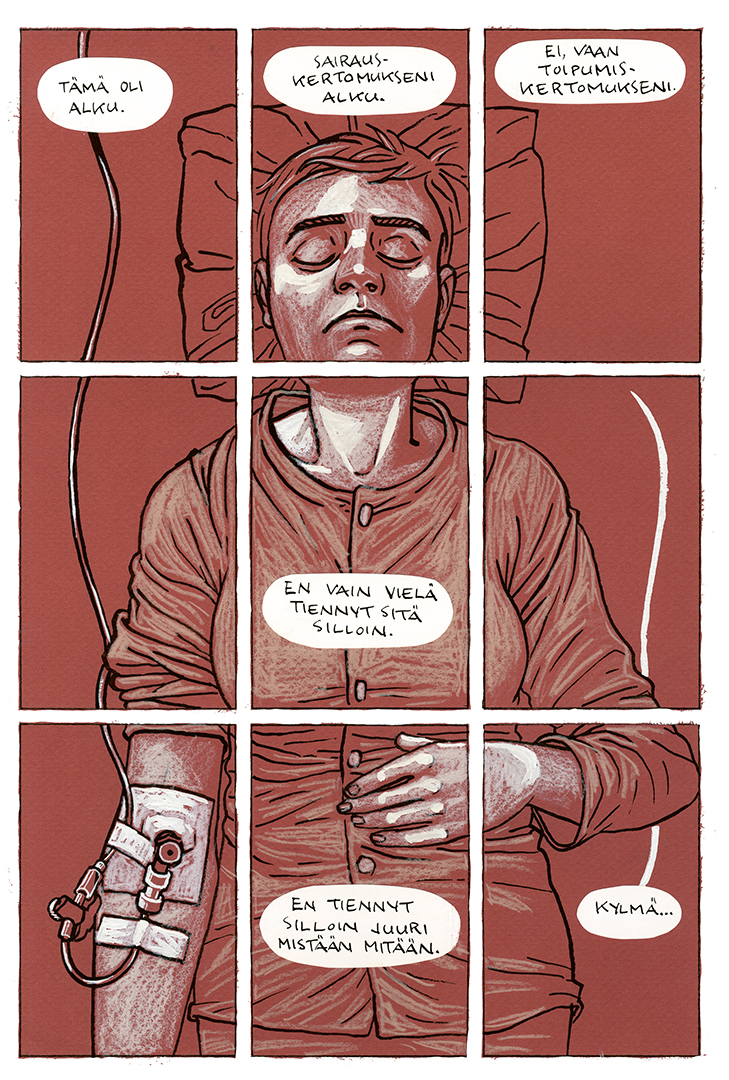

Memento Mori / Sarjakuvakirja / WSOY

Omaelämänkerrallinen kertomus vakavasti sairastumisesta. Saatavilla verkkokaupasta. Kääneetu englanniksi, ranskaksi ja puolaksi. Eisner-palkintoehdokas yhdysvalloissa.

Käsintekstattu, myös kannen tekstit.

Memento Mori / Sarjakuvakirja / WSOY

Klikkaa nähdäksesi lisää projektista.

Memento Mori / Sarjakuvakirja / WSOY

Omaelämänkerrallinen kertomus vakavasti sairastumisesta. Saatavilla verkkokaupasta. Kääneetu englanniksi, ranskaksi ja puolaksi. Eisner-palkintoehdokas yhdysvalloissa.

Käsintekstattu, myös kannen tekstit.

Memento Mori / Sarjakuvakirja / WSOY

Omaelämänkerrallinen kertomus vakavasti sairastumisesta. Saatavilla verkkokaupasta. Kääneetu englanniksi, ranskaksi ja puolaksi. Eisner-palkintoehdokas yhdysvalloissa.

Käsintekstattu, myös kannen tekstit.

Memento Mori / Sarjakuvakirja / WSOY

Omaelämänkerrallinen kertomus vakavasti sairastumisesta. Saatavilla verkkokaupasta. Kääneetu englanniksi, ranskaksi ja puolaksi. Eisner-palkintoehdokas yhdysvalloissa.

Käsintekstattu, myös kannen tekstit.

Memento Mori / Sarjakuvakirja / WSOY

Omaelämänkerrallinen kertomus vakavasti sairastumisesta. Saatavilla verkkokaupasta. Kääneetu englanniksi, ranskaksi ja puolaksi. Eisner-palkintoehdokas yhdysvalloissa.

Käsintekstattu, myös kannen tekstit.